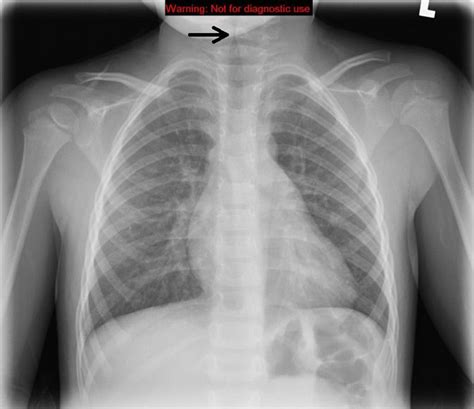

Web in radiology, the steeple sign is a radiologic sign found on a frontal neck radiograph where subglottic tracheal narrowing produces the shape of a church steeple within the trachea itself. Features demonstrating the steeple sign in keeping with croup. Distension of the hypopharynx is also seen due to the patient's attempt at decreasing airway resistance. Web the steeple sign (also called the wine bottle sign, and inverted v sign), refers to the tapering of the upper trachea on a frontal chest radiograph reminiscent of a church steeple, suggestive of croup. Seen on ap radiographs of the neck or chest and neck demonstrates uniform narrowing of the subglottic airway. Thumb sign is a term also used in other conditions: Web related to steeple sign: 2 case questions available annotated image zoomed image of the steeple sign, consistent with croup. Epiglottitis, croup, stridor, racemic epinephrine, tripod sign steeple sign the radiologic image of subglottic narrowing from edema, suggestive of a steeple, seen in croup. The steeple sign is seen on anteroposterior radiographs of the soft tissues of the neck.

2 case questions available annotated image zoomed image of the steeple sign, consistent with croup. Web in radiology, the steeple sign is a radiologic sign found on a frontal neck radiograph where subglottic tracheal narrowing produces the shape of a church steeple within the trachea itself. Notable causes and complications in acute respiratory failure Features demonstrating the steeple sign in keeping with croup. Thumb sign is a term also used in other conditions: 2 case questions available annotated image zoomed image of the steeple sign, consistent with croup. Seen on ap radiographs of the neck or chest and neck demonstrates uniform narrowing of the subglottic airway. Case discussion croup (laryngotracheitis) is a common diagnosis made in children six months to three years of age. Epiglottitis, croup, stridor, racemic epinephrine, tripod sign steeple sign the radiologic image of subglottic narrowing from edema, suggestive of a steeple, seen in croup. Web related to steeple sign: The steeple sign is seen on anteroposterior radiographs of the soft tissues of the neck.